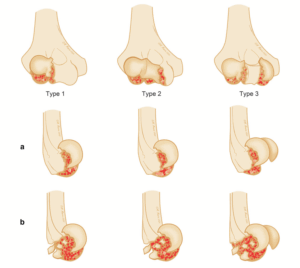

Recent studies have evaluated the progressive joint damage stages (from I to IV) according to the International Cartilage Research Society (ICRS) OCD grading on the basis of magnetic resonance imaging (MRI). (3)

It was demonstrated that, despite the different concave shape of the glenoid, its OCD follows the same progression over the time of the convex weight-bearing articular surfaces and needs, likewise, the same gradespecific management. Patients with IRCS OCD stage I and some with OCD stage II present with a stable shoulder and can undergo conservative treatment. Unstable or advanced glenoid OCD stages, characterized by disruption of the articular cartilage and the presence of separated fragments as loose bodies, require surgical treatment. Moreover, this is indicated when the conservative approaches fail, especially because of long-standing pain and joint range of motion worsening. Proposed surgical treatments include arthroscopic drilling, microfractures, debridement of the unstable osteochondral fragments, and fixation with suture anchor or autogenous osteochondral plugs, platelet-rich plasma, and gellike sodium hyaluronate. (2,4) There is not yet consensus regarding the ideal technique. In this Technical Note, we describe an arthroscopic procedure with a single-layer hyaluronate-based scaffold for the treatment of OCD of the glenoid.